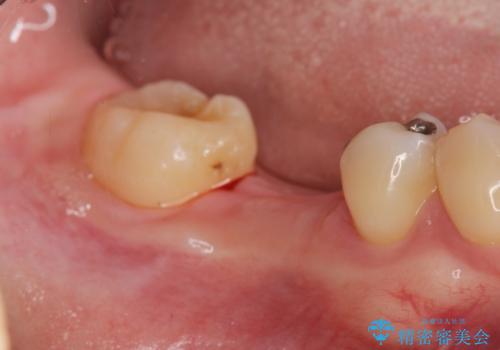

- 虫歯を数年放置した結果、痛みがひどくなり治療を希望され来院されました。

根だけ残った歯は、破折があり急性の炎症が認められ抜歯が必要な状態です。

抜歯後は、前後の歯を削らずにしっかりと咬合力を回復できるインプラント治療を選択されました。